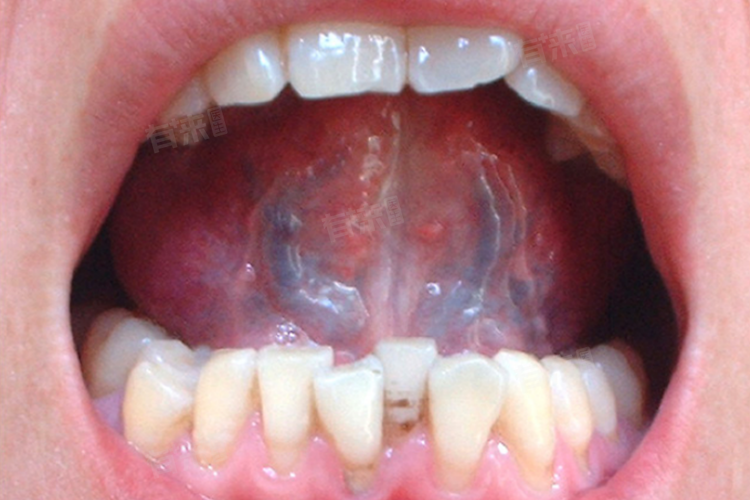

3、口腔扁平苔藓:是一种常见的口腔黏膜慢性疾病,特征为白色条纹或斑块,有时伴有红斑或溃疡。虽然主要症状出现在颊黏膜上,但它也可能累及舌部,导致舌下静脉扩张和颜色变暗,这是因为炎症反应影响了局部血流。

4、白斑病:表现为口腔黏膜上的白色斑块,而且由于细胞代谢异常,会影响局部微循环,造成舌下静脉扩张和色泽加深,这类病变需密切监测以防恶化成癌症。